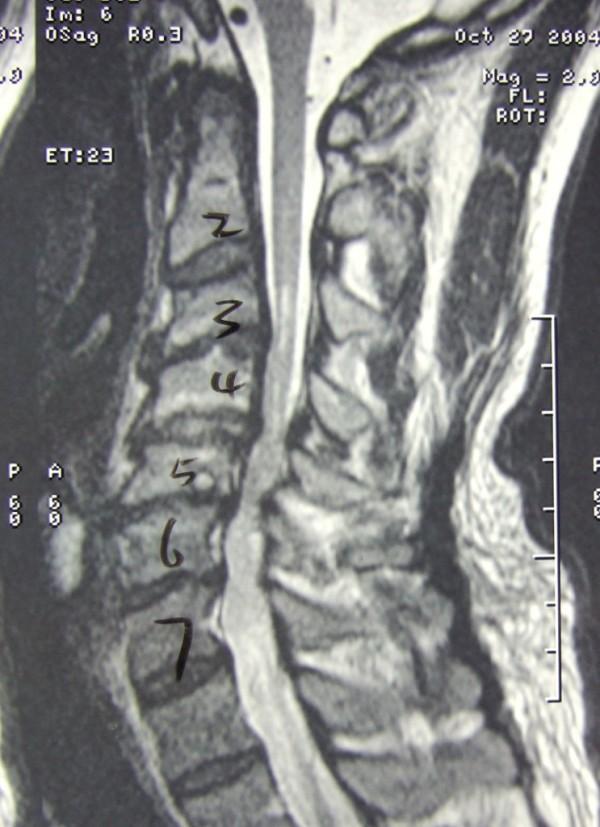

Eighteen patients (24.3%) presented with post operative upper limb palsy. Majority of patients presented with dysesthesia (17/18) and with deficit of the C5 segment (17/18). Ten patients presented with pure dysesthesia and 8 patients presented with mixed motor-sensory deficit and dysesthesia. Multilevel involvement was exclusively presented in patients with motor weakness. A longer duration of symptom (16.7 Vs 57.2 days) was noticed in patients in the motor deficit group. Average Pavlov ratio less then 0.65 (P = 0.027, Odds Ratio = 3.68) and compression at the C3/4 in preoperative MRI image (P = 0.025, Odds Ratio = 6) were significant risk factors for development of this problem.

Post operative upper limb palsy is not uncommon and thorough preoperative explanation is important. There is a spectrum of clinical presentation and patients with multi-level involvement and motor deficit are associated with poorer prognosis. Average Pavlov ratio < 0.65 and compression at C3/4 segment on preoperative MRI image are simple and reliable preoperative predictor for the development of this problem.

18例患者(24.3%)出现术后上肢麻痹。大多数患者表现为感觉异常(17/18)及C5节段功能障碍(17/18)。10例患者表现为单纯感觉异常,8例患者表现为运动 - 感觉混合功能障碍及感觉异常。多节段受累仅见于有运动无力的患者。运动功能障碍组患者的症状持续时间更长(16.7天对57.2天)。术前MRI图像中平均Pavlov比值小于0.65(P = 0.027,优势比 = 3.68)及C3/4节段受压(P = 0.025,优势比 = 6)是该问题发生的显著危险因素。

术后上肢麻痹并不少见,术前充分解释很重要。临床表现具有多样性,多节段受累及运动功能障碍的患者预后较差。术前MRI图像中平均Pavlov比值<0.65及C3/4节段受压是该问题发生的简单可靠的术前预测指标。